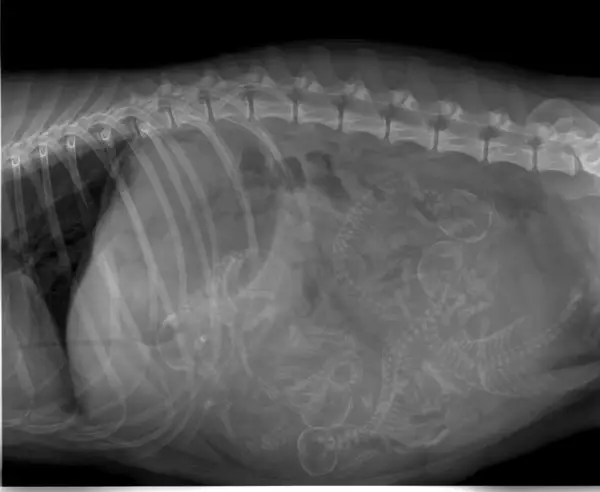

Side note: the “average” human has >1 skeleton within them.

Am I the only one seeing tiny alien kids from the Aliens movie?

I see 5 of them.

Pregnant women should avoid people that got a x-ray recently but dogs can have x-ray during pregnancy?(edit) wrong apparently, I don’t even know where I got this from

People and dogs who have been recently x-rayed are not a danger to others. They don’t suddenly start giving off radiation themselves (above background levels).

I’ve never heard about pregnant women having to avoid people who had a recent x-ray. According to the Mayo Clinic: “The possibility of an X-ray during pregnancy causing harm to a fetus is very small. Generally, the benefits of the information from an X-ray outweigh the risks.”

I think you might be confusing it with midly radioactive injections. My gf was given one to study how well her lyph nodes function and distribute the liquid. She was tol not to hang around pregnant people too long.

Hopefully dogs are more resistant to X-rays than we are : we stopped X-raying pregnant people because the babies had very high leukemia rates afterwards…